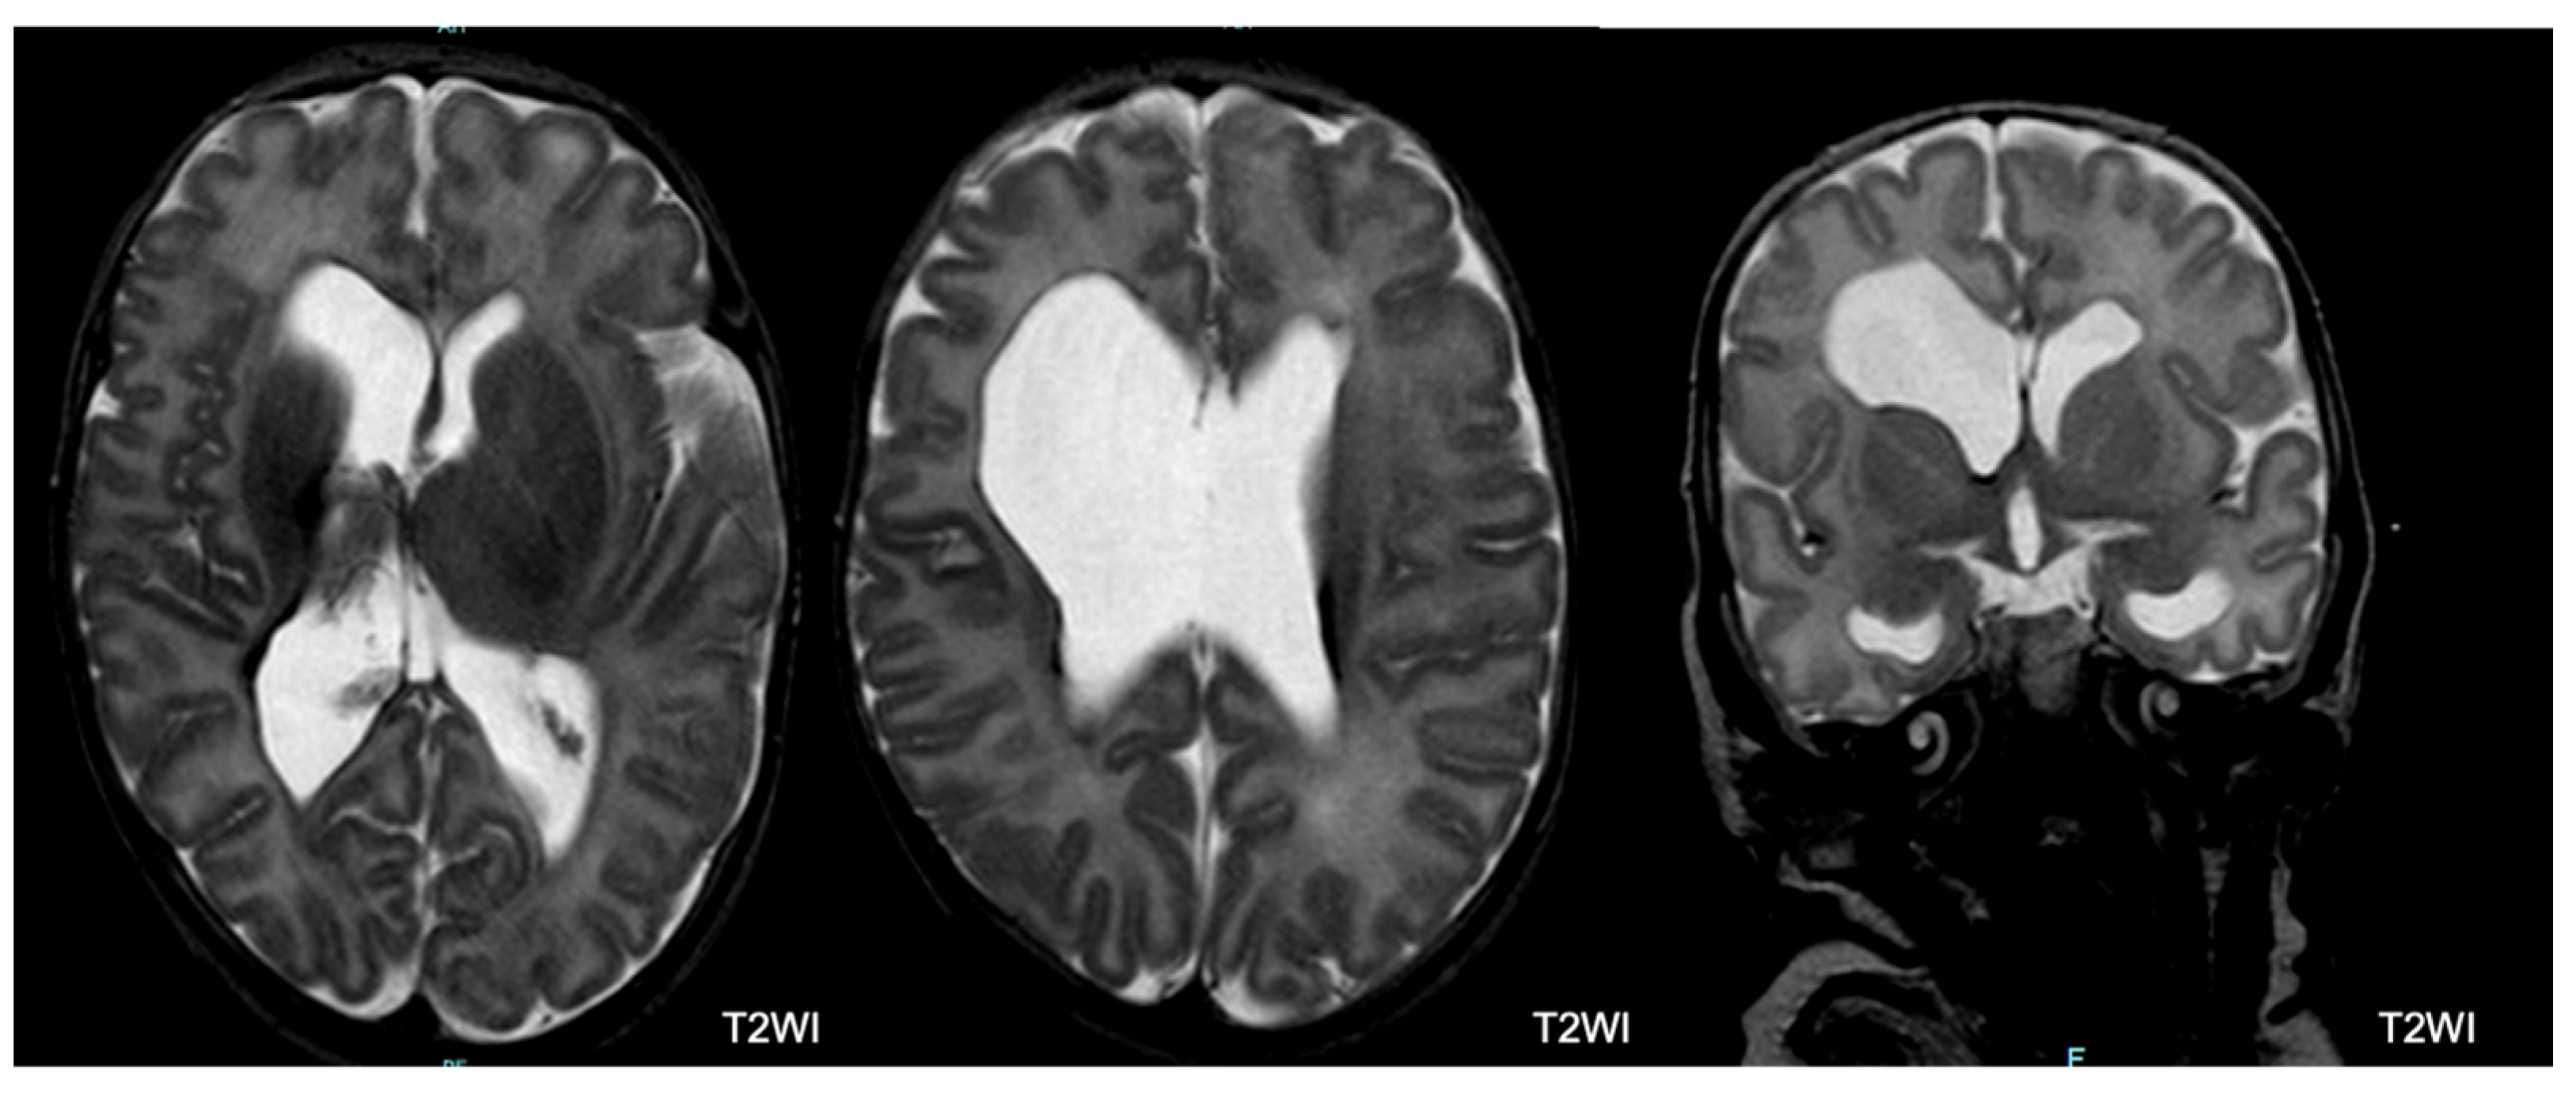

3.3. Brain Magnetic Resonance Imaging (MRI) Protocol and Classification

- Germinal Matrix Hemorrhage–Intraventricular Hemorrhage (GMH-IVH): The germinal matrix is a structure that is normally visible on imaging and undergoes involution as the fetus ages, leaving behind only remnants in the caudothalamic notch and roof of the temporal horns after 32 weeks of gestation. In our study, an irregular contour in a subependymal area with a low T2 signal or accompanying IVH was categorized as GMH-IVH. It is important to note that hemorrhage may not be immediately evident at TEA.

- Hemorrhagic Parenchymal Infarction (HPI): When fully developed, HPI is characterized by a focal bulging or outpouching of the ventricular contour, usually unilateral. This is often accompanied by a low T2 signal component, indicating previous hemorrhage.

- Periventricular Leukomalacia (PVL): PVL typically manifests as multiple bilateral periventricular cysts in a symmetric distribution, initially appearing separate from the ventricle. Solitary or unilateral cysts are more likely to be venous infarcts or connatal cysts. At TEA, the cysts may no longer be visible. Our study used the following criteria to diagnose PVL: residual bilateral periventricular cysts, dilated/angulated posterior aspects of the lateral ventricles, and associated white matter volume loss. This is often accompanied by thalamic atrophy and abnormal myelination.

- Punctate White Matter Lesions (PWML): PWML are small areas of injury in the white matter with no consistent sonographic appearance. In our study, PWML are defined as small foci of high T1 signal in the white matter, less commonly seen on T2 sequences. The conspicuity of these lesions decreases over time, suggesting a likely higher original lesion load.

- Subependymal Cysts: Subependymal cysts, characterized by thin walls, are typically located at the caudothalamic notch. These cysts may or may not be the sequelae of a germinal matrix hemorrhage.

- Cerebellar Hemorrhage: Cerebellar hemorrhage is defined by size, with small hemorrhages smaller than 5 mm and large hemorrhages larger than 5 mm. At TEA, cerebellar atrophy may be present with minimal evidence of hemorrhage. It is noteworthy to mention that the germinal matrix is located on the outer surface of the cerebellum, so hemorrhages may involve the cerebellar cortex.

- Abnormal Myelin: Abnormal myelin is defined as a diffuse excessively high T2 signal intensity in the subcortical white matter.

- Unclassified Lesions: This category included findings that did not conform to the lesion definitions above. Lesions were considered major if associated with lobar tissue or multiple areas of tissue loss.

5.2. Brain MRI Abnormalities

5.3. MRI and Outcome